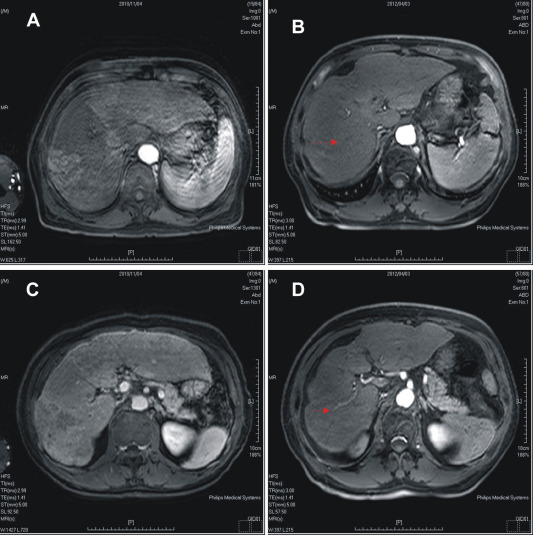

Palliative radiation therapy (three-dimensional conformal radiotherapy) was given 5 days per week at 1.8 Gy per day to the portal vein and tumor of the right lobe for 28 fractions to a total dose of 50.4 Gy; treatment with sorafenib (400 mg per day) was started on December 10, 2010. Fig. 1 A1,B1 and A2,B2 shows the dose distribution for the tumor, portal vein, and surrounding organs and tissues.

Computed tomography scans of our patient with hepatocellular carcinoma showing ...

Figure 1.

Computed tomography scans of our patient with hepatocellular carcinoma showing dose distribution of radiation from proton beam therapy (A) and that from standard X-rays using the same beam arrangement (B). The 100%, 95%, 80%, and 50% isodose lines are represented in red, yellow, light blue, and dark blue, respectively. The planning target volume (PTV) is represented in pink. The protocol required the PTV to be encompassed by the 95% dose envelope. (A1), (B1) On liver tumor. (A2), (B2) On portal vein. GTV = gross tumor volume.